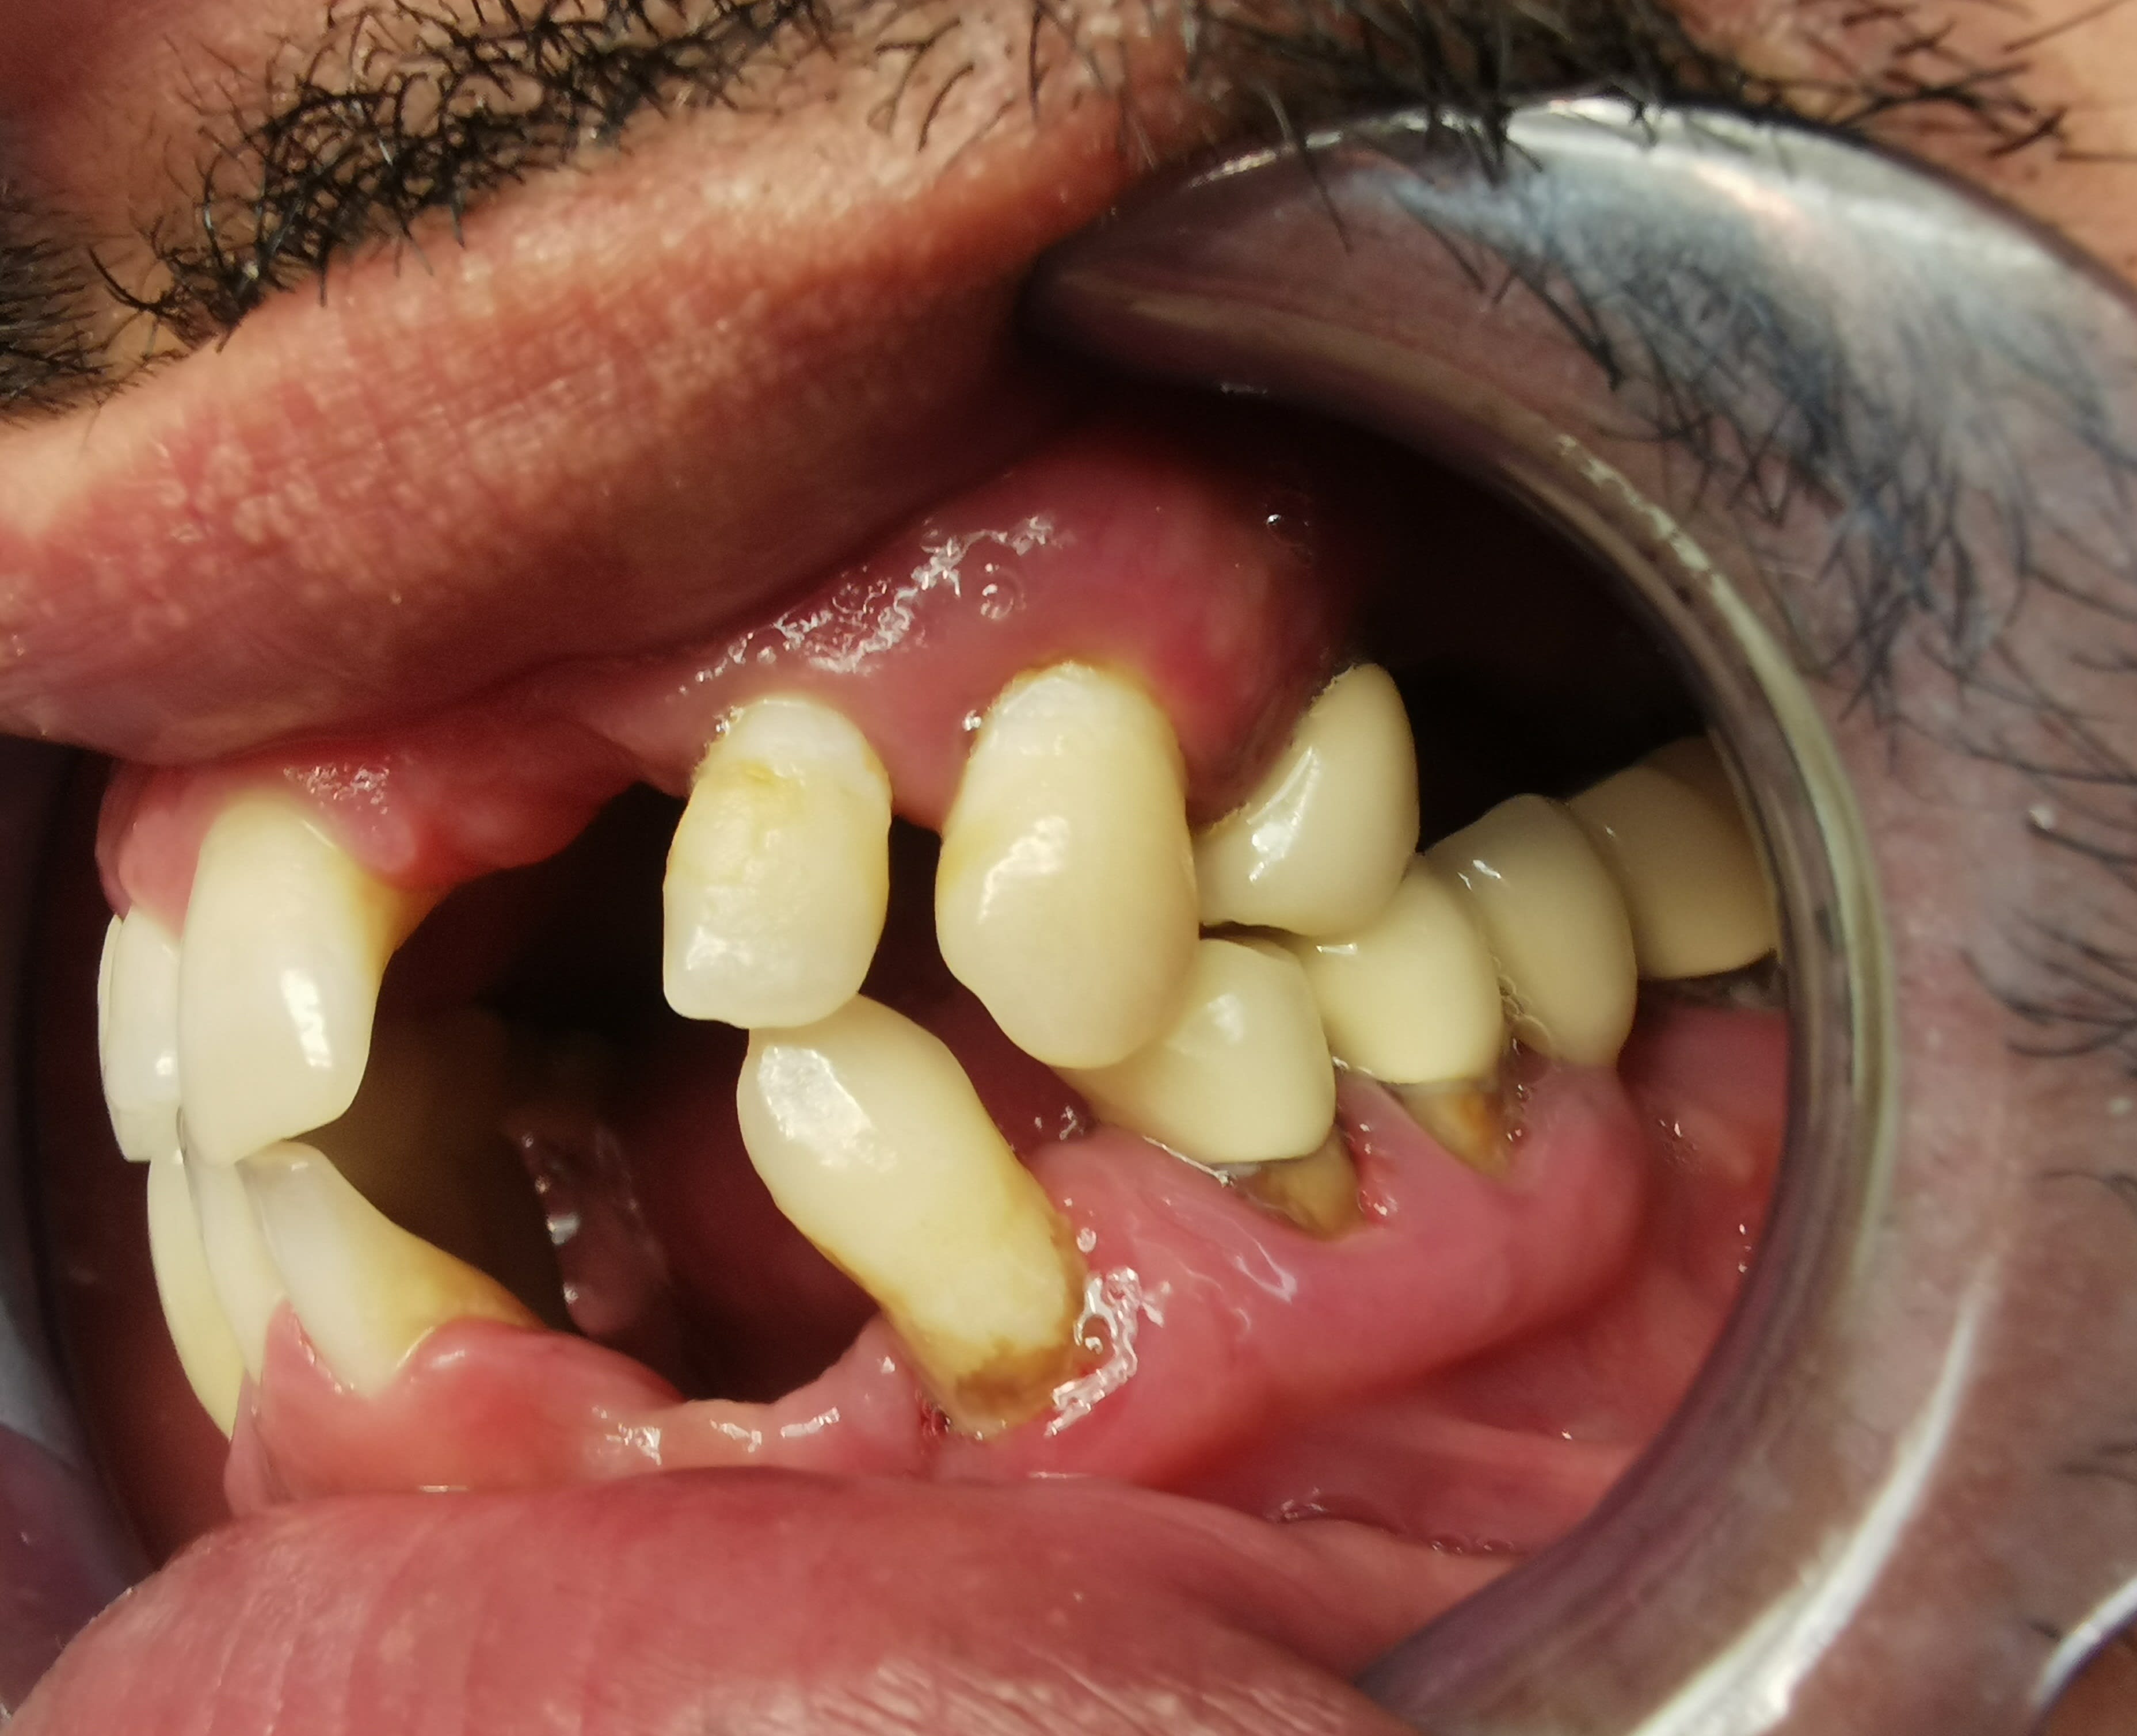

en intra buccal

Paro +++

bridge sect 1 cassé, avec mobilité ++ sur 15 et

mobilité +++ sur 22 24 et plus modérée au niveaudu bridge sect 3

Quelles dents serait il possible de conserver ?